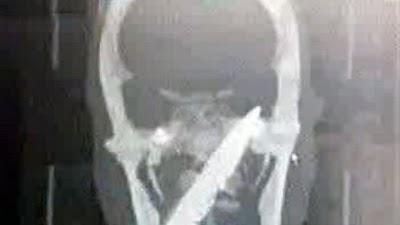

Hasta que llegó al Hospital del Pueblo en Yuxi, provincia de Yunnan, allí explicó por enésima vez sus males, en esta ocasión se ordenó una serie de radiografías y exámenes de TAC (Tomografía Axial Computarizada)... y sorpresa, allí estaba la fuente de sus males, hubo que operarlo urgentemente y lograron sacarle la hoja del cuchillo de unos 10 cms. de largo.

---Radiografía de Li con el cuchillo dentro de su cráneo, tomado de www.friki.net